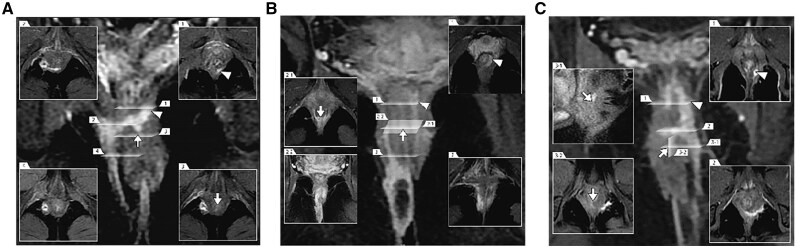

背景与目的:高复杂性肛瘘是肛肠科医师面临的临床挑战,也是患者的噩梦。尽管保留括约肌入路似乎是一种理想的手术干预,但在治疗效果上仍有改进的余地。在此,我们介绍了一种增强的保留括约肌入路,即内括约肌皮瓣(FOISF)瘘闭塞治疗高度复杂的肛瘘。方法:本研究评估了中山大学附属第六医院(中国广州)于2021年10月至2022年12月期间接受FOISF治疗的15例高度复杂肛瘘患者。对成功率、肛门功能和各种手术特征的数据进行了严格的分析。结果:所有患者均行FOISF手术,中位手术时间为53分钟。14例患者实现了第一次意向愈合,1例患者实现了第二次意向愈合。随访14 ~ 30个月无复发。所有患者均表现出满意的肛门控制,术前与术后Wexner评分差异无统计学意义(P = 0.331)。与术前评估相比,观察到生活质量有显著改善(P < 0.001)。结论:FOISF手术是治疗高度复杂肛瘘的有效方法。

Background and aim: High complex anal fistula is a clinical challenge for proctologists and a nightmare for patients. Although the sphincter-sparing approach seems an ideal surgical intervention, there remains room for improvement in treatment efficacy. Herein, we introduce an enhanced sphincter-sparing approach, namely the fistula occlusion with the internal sphincter flap (FOISF), for treating high complex anal fistulas.

Methods: This study evaluated 15 patients with high complex anal fistulas who underwent FOISF between October 2021 and December 2022 in the Sixth Affiliated Hospital, Sun Yat-sen University (Guangzhou, P. R. China). Data on success rates, anal function, and various surgical characteristics were subjected to rigorous analysis.

Results: All patients underwent the FOISF procedure, with a median operation time of 53 min. Fourteen patients achieved primary intention healing, while one patient healed by second intention. No recurrence was observed over a follow-up period of 14-30 months. All patients exhibited satisfactory anal continence, with no statistically significant difference observed between preoperative and postoperative Wexner scores (P =0.331). A significant improvement in the quality of life was observed when compared with the preoperative assessment (P <0.001).

Conclusion: The preliminary results of the FOISF procedure present an effective approach to treat high complex anal fistula.